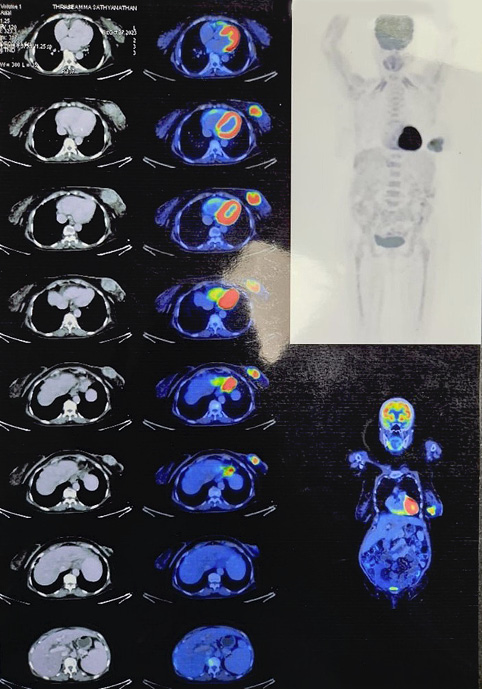

An 80-year-old female k/c/o HTN, COPD, hypothyroidism, and JAK 2 mutation positive polycythaemia vera presented with lump left breast of 8 months duration. No history suggestive of locoregional or distant metastases. On examination 6x4 cm lump retro areolar region, irregular surface, hard in consistency, fixed to breast tissue and overlying skin, not fixed to the chest wall. No palpable axillary lymphadenopathy, examination of right breast was normal. Sono mammogram showed Lobulated hypoechoic lesion measuring 4.4x3.2x4.7 cm from 5 to 7 o’clock region in retro and periareolar region – BIRADS-V. Two clustered areas of pleomorphic calcifications in upper outer and central quadrants – BIRADS-4b (Figure 1). F18 FDG PET CT scan showed large heterogeneously enhancing FDG avid soft tissue mass with spiculated margins measuring 46x42x43 mm (max SUV – 13.2) in retro areolar region extending to lower quadrant. The lesion is seen abutting the overlying skin, the planes with underlying muscles maintained. No abnormal enhancing or FDG avid lesion in brain, lungs, liver, adrenal or skeleton (Figure 2). USG guided Core needle biopsy was done which revealed metaplastic carcinoma of adenosquamous type. ER, PR-positive, HER 2 Neu-Negative.

Figure 2. PET CT images showing large heterogeneously enhancing FDG avid soft tissue mass with spiculated margins measuring 46x42x43 mm (max SUV – 13.2)